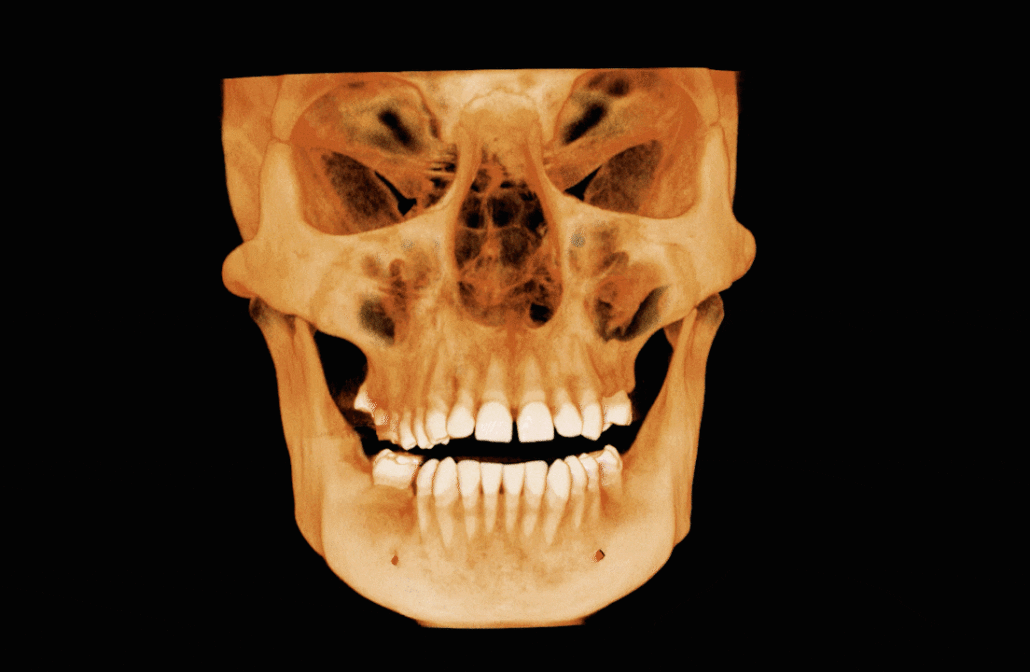

There is coverage of all the nasal cavities and paranasal sinuses apart from the most superior parts of the frontal sinuses. There is deviation of the nasal septum to the right side, with a bony spur projecting into the right middle meatus. Asymmetries of the turbinate bones are associated with this, with relatively larger turbinates on the left side and with a paradoxical curvature of the left middle turbinate. No mucosal disease in the nasal cavities. The maxillary antra are aerated normally apart from very limited mucosal thickening at the medial part of the antral roof on the right side, close to the natural ostium. The ostia are patent bilaterally (image 1). Other paranasal sinuses are normally aerated. The deviation of the nasal bone anatomy has an effect on the width of the frontal recess (the drainage channel of the right frontal sinus leading into the ostio-meatal complex), but it is patent. Overall, the ostio-meatal complexes are patent bilaterally and the nasal cavity and paranasal sinus health is clear.

Image 1

Coronal cross-section through the maxillary antra and their ostia